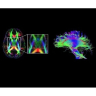

Новые возможности

В системе SIGNA PET/MR есть все инструменты, необходимые для выявления маркеров разных заболеваний и для создания новых протоколов. ПЭТ/МРТ можно использовать совместно с мультиядерной спектроскопией в лаборатории in vivo для изучения быстрых биохимических процессов. Кроме того, PET ToolBox и набор инструментов Orchestra предоставляют персональный доступ к функциям реконструкции изображений для ПЭТ и МРТ, ускоряя и упрощая работу с необработанными данными.

• Специальный пакет приложений для измерения и сравнения объемных изображений ЦНС с нормами поможет вам в диагностике нейродегенеративных заболеваний, а дополнительные инструменты визуализации — в постановке точного диагноза с помощью бета-амилоидов и радиоизотопных маркеров ФДГ.

• In vivo лаборатория — получайте полные данные биохимических процессов in vivo с мультиядерной спектроскопией на SIGNA PET/MR.